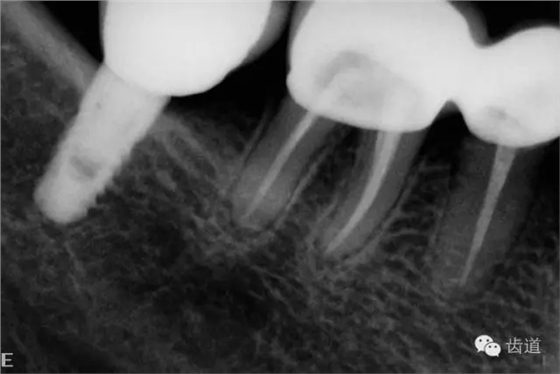

2、45,46術(shù)前片顯示根管上段充填物,根管影像不清晰,少許根尖暗影

6、45,46,47牙片